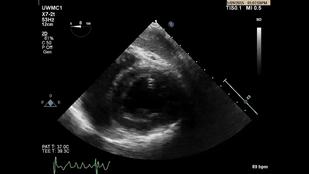

• Обложка: Рис. 3.6 Визуализация из трансгастрального доступа. Видео Б Позиция приточного отдела правого желудочка (ПЖ).

• Обложка: Рис. 3.6 Визуализация из трансгастрального доступа. Видео В Позиция среднего отдела левого желудочка по короткой оси